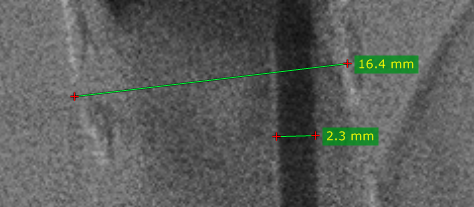

从 测量 下拉菜单中选择 长度(或按 L 键)。

将光标移到起点处,按住鼠标左键拖动画出线段,松开鼠标完成测量。

测量结果以毫米或像素显示(当图像文件中不包含校准数据时以像素显示)。

按住鼠标左键拖动线段本身或其端点,可移动整段线或调整端点位置。标注文字也可拖动到更合适的位置。

绘制线段时按住 Shift 键,可强制线段水平或垂直。